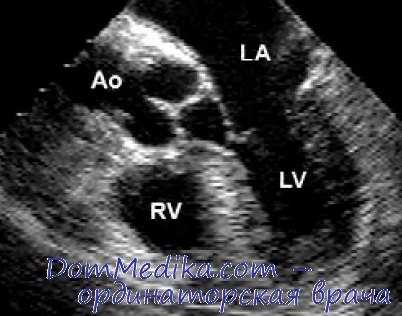

ЭхоКГ (эхокардиография) трансторакальная

В повседневной практике ЭхоКГ выполняют трансторакально. Исследователь сидит справа или слева от пациента, одной рукой держит датчик, другой - управляет настройками прибора, сосредоточиваясь при этом на изображении на экране монитора. Место локации и положение датчика определяют получаемое изображение. Качество получаемых ЭхоКГ-изображений зависит как от квалификации исследователя, так и от особенностей пациента. Трудно проводить исследование у больных с эмфиземой легких (например, страдающих ХОБЛ или находящихся на искусственной вентиляции легких), деформацией грудной клетки или выраженным ожирением, хотя практически у любого пациента можно найти, по крайней мере, один доступ с приемлемой визуализацией.

Трехмерная эхокардиография (3D-ЭхоКГ) трансторакальная

В настоящее время существует три варианта получения трехмерного изображения сердца: «живая» трехмерная ЭхоКГ (Live 3D) - в объеме усеченного конуса с углом сектора 30º, трехмерная ЭхоКГ в полном объеме (Full-volume) - с более широким углом лоцирования (пирамида 80º) и трехмерное цветное картирование (3D Color).

При обычном эхокардиографическом исследовании со стандартным обеспечением не представляется возможным получить множество параллельных срезов желудочка по короткой оси, и свое реальное воплощение эта идея получила только с появлением метода трехмерного моделирования ультразвукового изображения. Главное преимущество метода трехмерной реконструкции - возможность отказа от геометрических допущений и измерение объемов желудочка с учетом его конкретной формы.

Трехмерное изображение позволяет не только измерить объемы и фракцию выброса желудочка с измененной геометрией, но также определить локализацию и измерить объем аневризмы левого желудочка, что имеет несомненное значение в кардиохирургии.